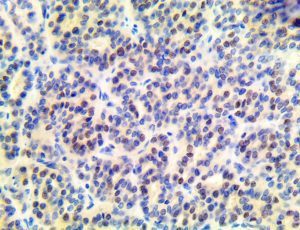

It is the ICU physician who is most likely to witness one of the deadliest manifestations of the abnormal immunological response, the cytokine storm syndrome (CSS). This response is also referred to by some as the cytokine release syndrome (CRS). CSS is characterized by continuous activation and expansion of macrophage and lymphocyte populations, which secrete large amounts of cytokines, causing the cytokine storm. This massive cytokine release is akin to hemophagocytic lymphohistiocytosis (HLH) disease, a syndrome characterized by initial unchecked and persistent activation of cytotoxic T lymphocytes and NK cells.

Clinical and laboratory manifestations of HLH include fever, enlarged liver and/or spleen, neurologic dysfunction, coagulopathy, liver dysfunction, cytopenias (i.e., low levels of erythrocytes, leukocytes, and/or platelets), hypertriglyceridemia, hyperferritinemia, hemophagocytosis, and eventually diminished NK cell activity as the immune system becomes progressively paralyzed. HLH can be familial (primary HLH) or secondary to another disease process (sHLH), such as rheumatic disease, in which it is referred to as macrophage activation syndrome (MAS, characterized by elevated ferritin).